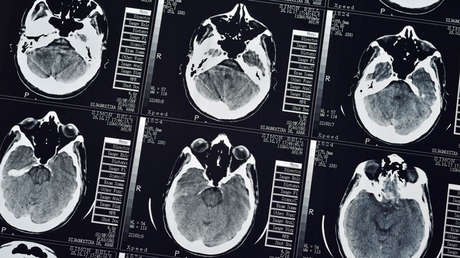

Un hombre apellidado Wang fue operado a finales de octubre en un centro médico de la provincia china de Guangdong con el fin de extraer de su cerebro un parásito vivo de 12 centímetros de largo que se estaba alimentando de sus tejidos desde hace 15 años.

El neurocirujano Gu Youming, quien dirigió exitosamente la intervención de más de dos horas, explicó que en caso de no haber sido extirpado, el animal habría seguido comiendo masa cerebral, lo que podría haber dejado al hombre paralizado o, incluso, poner en peligro su vida.

No fue hasta 2018 cuando a Wang le diagnosticaron finalmente la infección parasitaria. Al principio, optó por métodos de medicina tradicional para intentar eliminar la tenia, pero después de sufrir otro episodio de convulsiones decidió someterse a la cirugía.